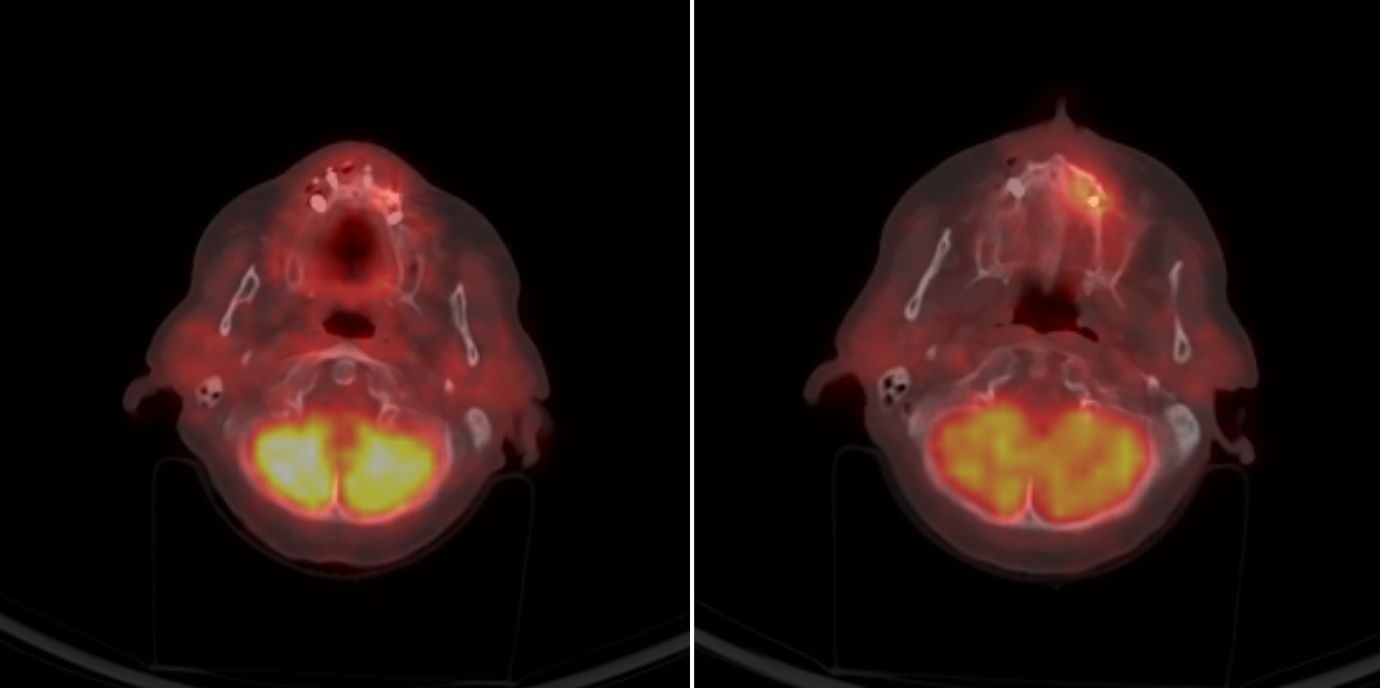

PET-CT-Bilder machen Entzündungsherde im Kiefer sichtbar. Dadurch ermöglichen sie es, frühzeitig und sehr genau vorherzusagen, wo sich unter Denosumab eine Kiefernekrose entwickeln könnte. Christine Brunner und Miriam Emmelheinz haben mit ihrem Team an der Univ.-Klinik für Gynäkologie und Geburtshilfe Patientinnen untersucht, die an Brustkrebs mit Knochenmetastasen erkrankt sind und sie haben einen Weg gefunden, wie Kiefernekrosen von vornherein verhindert werden können.

Im PET-CT leuchten Entzündungsherde am Kiefer auf. Nuklearmediziner:innen können anhand dieser Bildgebung fast bis auf den Zahn genau vorhersagen, wo sich in den kommenden durchschnittlich 238 Tagen die Kiefernekrose entwickeln wird – falls sich eine Kiefernekrose entwickelt. „Das ist wichtig“, wie Christine Brunner betont. Denn nicht jede Patientin mit einem Zahnherd, die sie im Rahmen ihrer Studie betreut hat, bekam eine Nekrose. „Aber geradezu jede, die eine Nekrose entwickelt hat, hatte vorher einen Zahnherd und zwar genau an der Stelle, an der später die Nekrose auftrat“, sagt Brunner. Die Gynäkologin ist Letztautorin, Miriam Emmelheinz firmiert als Erstautorin der Studie, die kürzlich in eClinicalMedicine (The Lancet-Gruppe) erschienen ist.

Mit einer Vorhersagezeit von im Mittel 238 Tagen und hoher Genauigkeit können Veränderungen im Kiefer lange vor der klinischen Symptomatik identifiziert werden. Dafür haben die Gynäkolog:innen von Nuklearmediziner:innen PET-CT- Bilder begutachten lassen, die vor Therapiebeginn mit Denosumab sowie alle drei Monate weiter im Verlauf aufgenommen wurden.